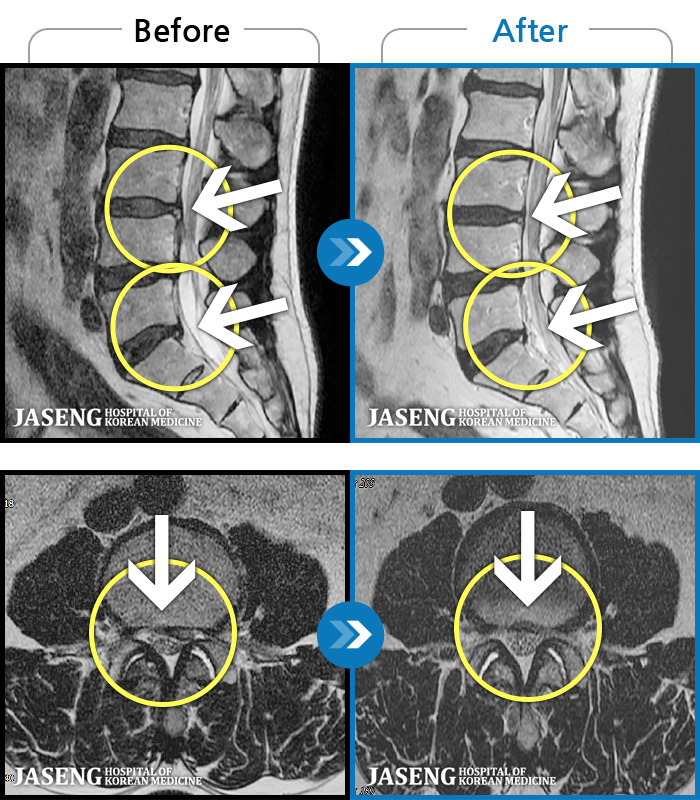

[뱸] 19.11.28~25.05.06

ȯںп Ǹ ǿ ԿǾ, ο ġ ۿ Ƿ ġḦ Ͻñ ٶϴ.